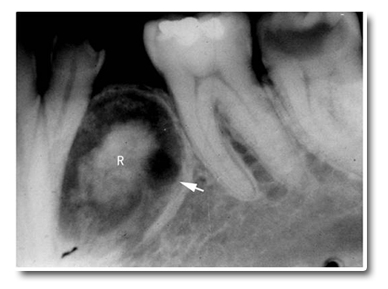

20~60岁之间,平均年龄为40岁左右;无性别差异;下颌比上颌多见,尤其前磨牙和磨牙区;外周型牙源性钙化上皮瘤多发生于前牙区;颌骨逐渐膨胀;X线表现为不规则透射区内含大小不等的阻射性团块,这些不透光团块常与未萌牙的牙冠部相邻近。病变透射区的周边与正常的分界较清楚,但骨硬化带不明显。